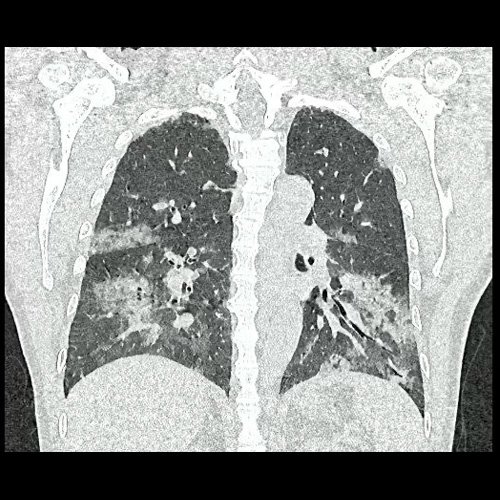

• Tomografía de tórax sin contraste endovenoso (Dia 0):Se observan múltiples áreas de consolidación parenquimatosa con broncograma aéreo y de distribución difusa por ambos pulmones, predominando en los lóbulos inferiores, asociadas a engrosamiento de los septos y rodeadas de tenue vidrio esmerilado. Se identifican estructuras ganglionares lateroaórticas, pretraqueales y subcarinales, ninguna de ellas sin alcanzar rango megálico.

Tomografia de torax sin contraste endovenosos (Ventana pulmonar- Corte coronal)